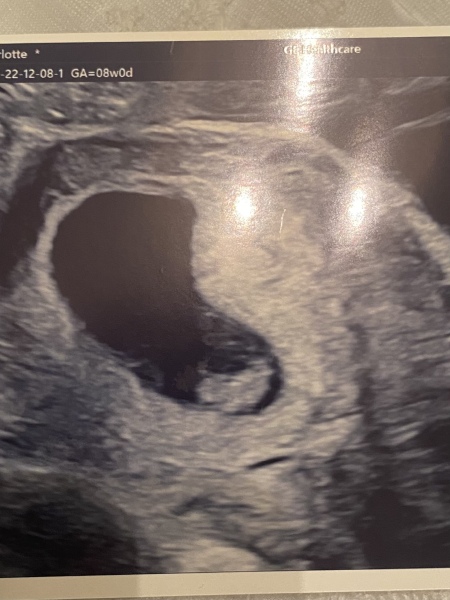

GGxxx · 08/12/2022 18:26

8 weeks little raspberry! Feel so better after having an early scan feel like your making it up before you see it on the screen!

Due July 2023

@GGxxx Ahhh what a lovely scan. Was that internal or external they did it?

@rach971 was external! Made me cry seeing the little heartbeat. Xx